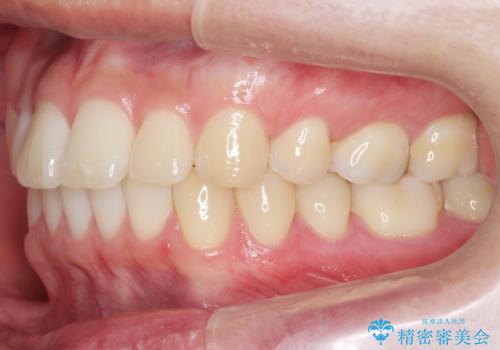

抜歯矯正の長期予後(術後8年目)

- ワイヤー矯正による治療後7年以上経過した患者様です。当時上の小臼歯を2本抜歯しています。

10代で矯正治療を行い、現在20代になられています。

矯正後8年目になりますが、並びも綺麗に保持でき、また上下の歯がさらにしっかり咬んできているのがわかります。

定期的にメンテナンスにきていただき、特に歯の健康状態にも問題がありません。

下は歯につけるタイプのワイヤーを貼っています。

上は取り外し式の装置を就寝時使っていただいています。

さしたる問題もなく、半年~1年に一度のメインテナンスにお越しになっている患者様です。保定装置については、慣れれば習慣化するためさほど負担ではありません。

矯正をしなくても起こる下の前歯のがたつきも予防でき、若々しい歯並びを維持することができます。